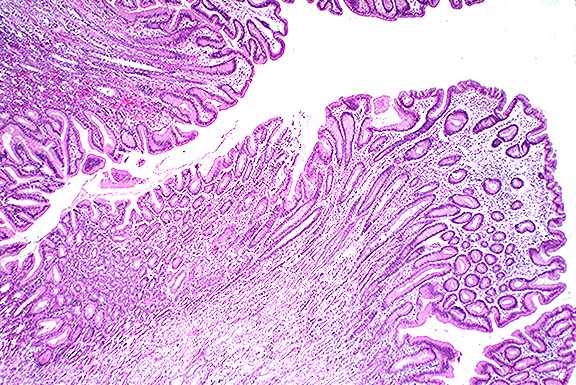

При эндоскопическом исследовании картина утолщенных складок видна отчетливо, можно оценить их окраску, наполненность кровью, наличие эрозий на вершинах складок и в межскладочном пространстве. Биопсия при этом заболевании имеет диагностическую ценность только в случае забора материала с большого участка визуально измененной слизистой с захватом железистого слоя, поэтому проводится по показаниям и, чаще всего, для дифференциальной диагностики.